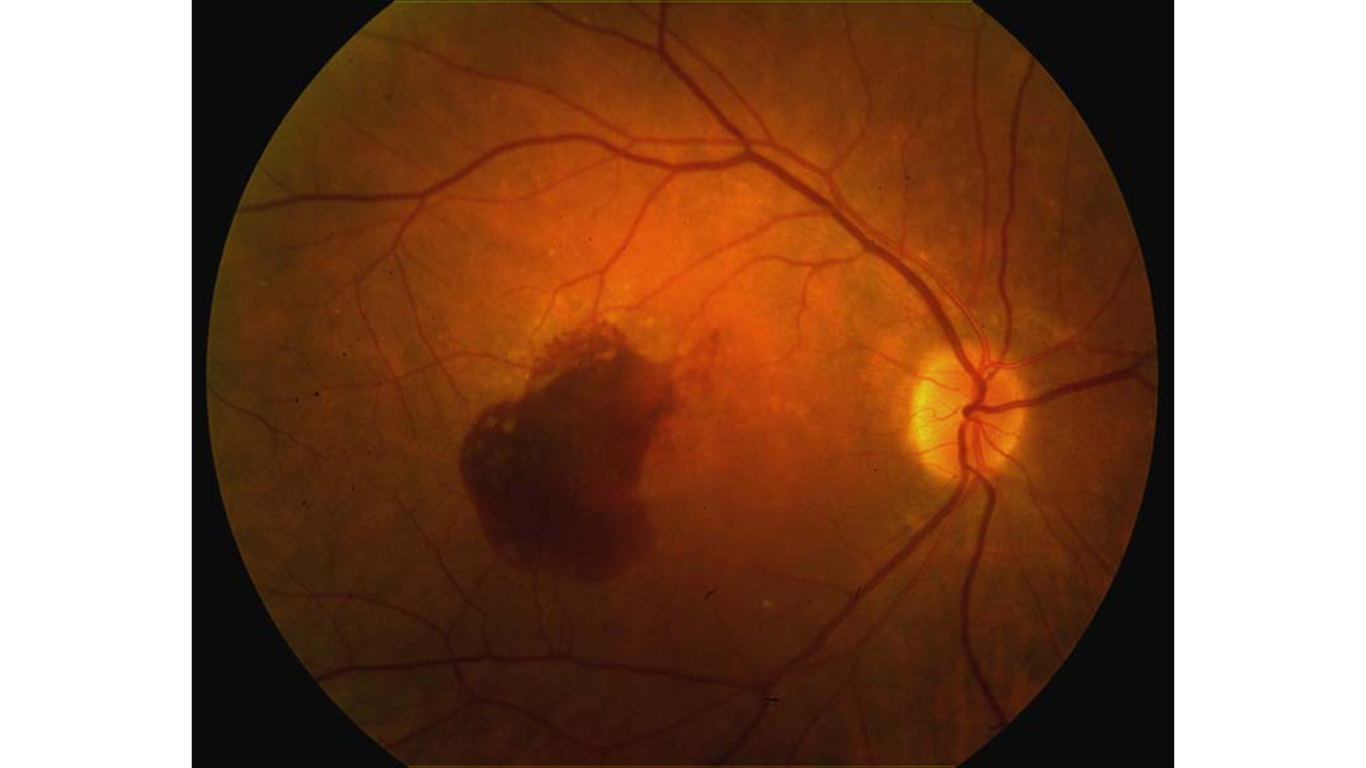

Thoái hóa điểm vàng do tuổi tác

Thoái hóa điểm vàng do tuổi tác (Age-related Macular Degeneration - AMD) là một câu chuyện buồn nhưng phổ biến về thị lực khi chúng ta già đi. Đây không chỉ là một bệnh lý về mắt mà còn là hành trình đối mặt với sự thay đổi về cách chúng ta cảm nhận thế giới....